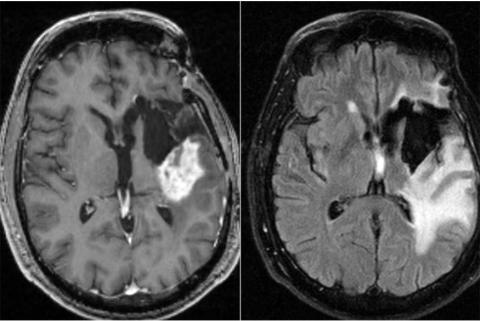

CHRONOTHÉRAPIE : La chimio le matin plus efficace contre le glioblastome

Plusieurs études ont déjà suggéré l’intérêt de la chronothérapie dans le traitement des cancers, la croissance incontrôlée des cellules cancéreuses étant souvent associées à des oncogènes qui perturbent le cycle circadien. Cette recherche d’une équipe de l'Université de Washington suggère à nouveau que le moment choisi pour la chimiothérapie pourrait influencer sur son efficacité. Ces données, présentées dans la revue Neuro-Oncology Advances sont tout particulièrement cruciales, ici pour le traitement du glioblastome, un type agressif de cancer du cerveau, à mauvais pronostic.

Le glioblastome est incurable. La survie moyenne après le diagnostic est estimée à 15 mois, avec une espérance de survie à 5 ans de moins de 10%. Alors que de nombreux essais cliniques sur de nouveaux candidats sont en cours, cette étude suggère qu'un ajustement mineur du traitement standard actuel, soit administrer la chimiothérapie le matin plutôt que le soir, pourrait déjà prolonger la survie des patients de plusieurs mois.